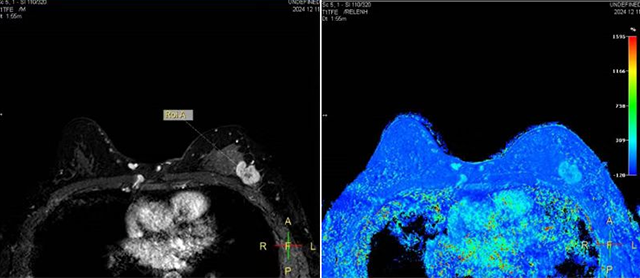

患者女性,37岁,入院后确诊左乳癌,详细询问病史、体格检查及影像学资料,乳腺外二科徐贵颖主任反复完善手术方案,她分析,该患者年龄较轻,因肿物累及乳头,伴有 乳头溢液,不具备保乳条件,双侧乳房极不对称,健侧乳房下垂,腹部皮肤相对松弛,皮下脂肪多,组织量充足。在与患者充分沟通交流后,结合患者情况,综合考虑,拟实施腔镜下保留乳头乳晕皮下腺体切除术联合横行腹直肌肌皮瓣(TRAM)乳房重建手术及对侧双环法缩乳术。腔镜下保留乳头乳晕的皮下腺体切除,切口隐蔽,视觉冲击小,降低对患者的心理伤害。同时联合TRAM再造乳房,兼有乳房塑形和腹部整形的双重效果,并节省了假体置入的费用,兼顾美观、安全与经济效益。结合健侧的缩乳成形术再造出两侧对称、有一定膨隆和下垂。弧线优美的乳房,以及理想的腹部形态。

横行带蒂腹直肌肌皮瓣转移乳房重建术(Transverse Rectus Abdominis Myocutaneous flap,TRAM)将下腹部皮肤、脂肪及腹直肌带蒂转移至胸部创面,根据对侧乳房大小及形态对再造乳房进行塑形,是一项难度很高的自体乳房再造术式。